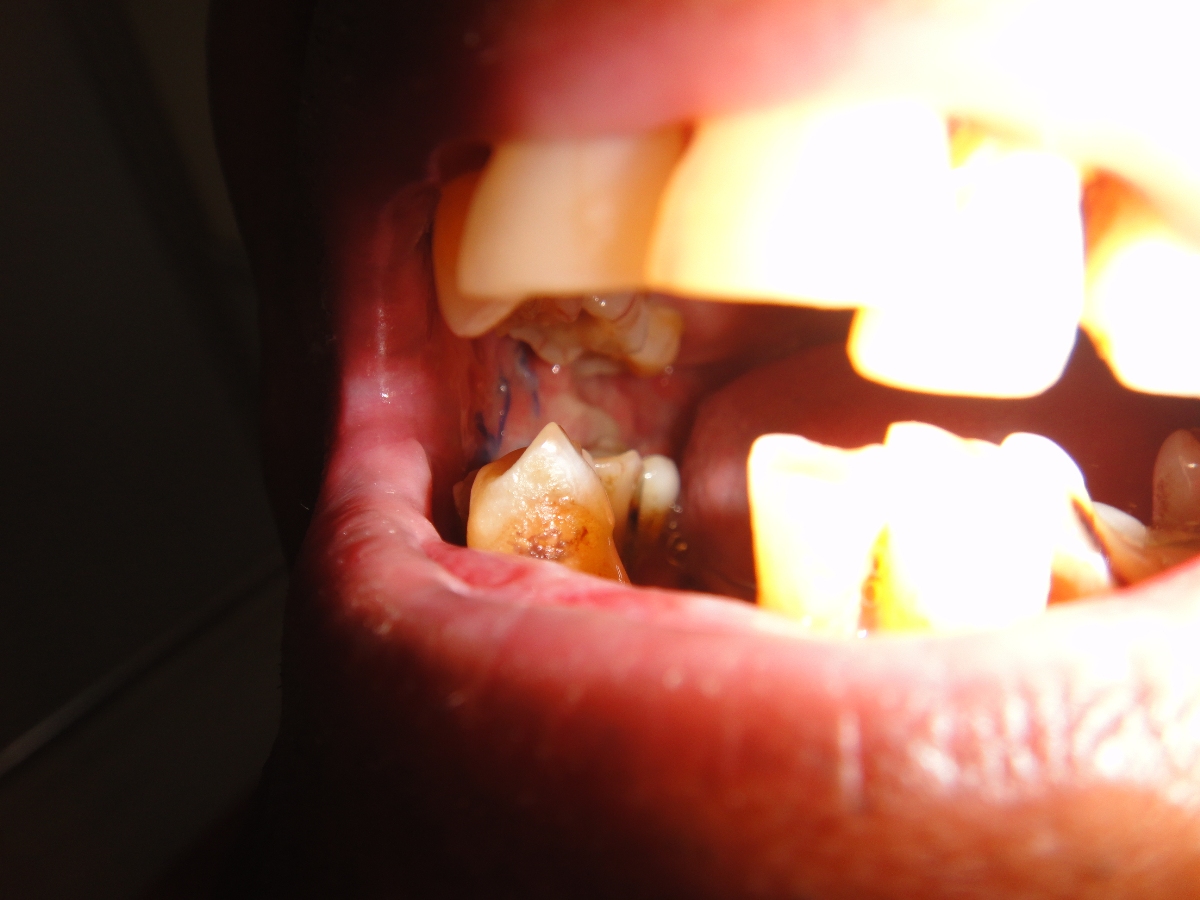

75 yrs old patient having right upper alveolus carcinoma.patient was operated for right buccal mucosa carcinoma in 2009.pet ct shows localised disease with minimal uptake in left neck node.Right subtotal maxillectomy done with Right PM flape.